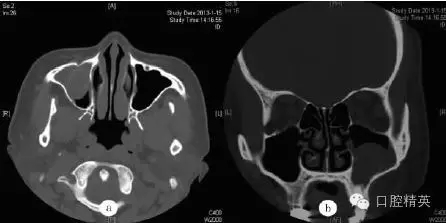

鼻竇CT檢查示:右側(cè)尖牙牙根處有一類圓形軟組織密度影(圖a),病變向上進入右側(cè)上頜竇,其內(nèi)見弧形線狀高密度影,鄰近牙槽骨壓迫性骨吸收(圖b)??紤]為根尖囊腫并發(fā)感染(右)。

圖a:術(shù)前水平位CT檢查顯示右側(cè)上頜竇黏膜囊腫,中央有類圓形影;圖b:術(shù)前冠狀位CT檢查顯示右側(cè)上頜竇黏膜囊腫并根尖骨質(zhì)吸收,含類圓形影;